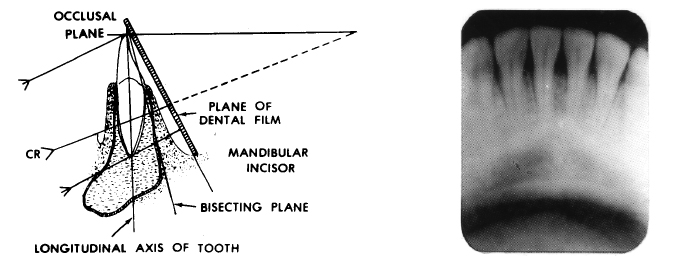

Oral maxillofacial radiology

Uses digital imaging to locate tumors and infectious diseases of the jaws, head, and neck, and assists in the diagnosis of patients with trauma and temporomandibular disorders

incorrect film placement

incorrect horizontal angulation/ overlap

vertical angulation too steep/foreshortened

verticlal anglulation too flat/ elongation